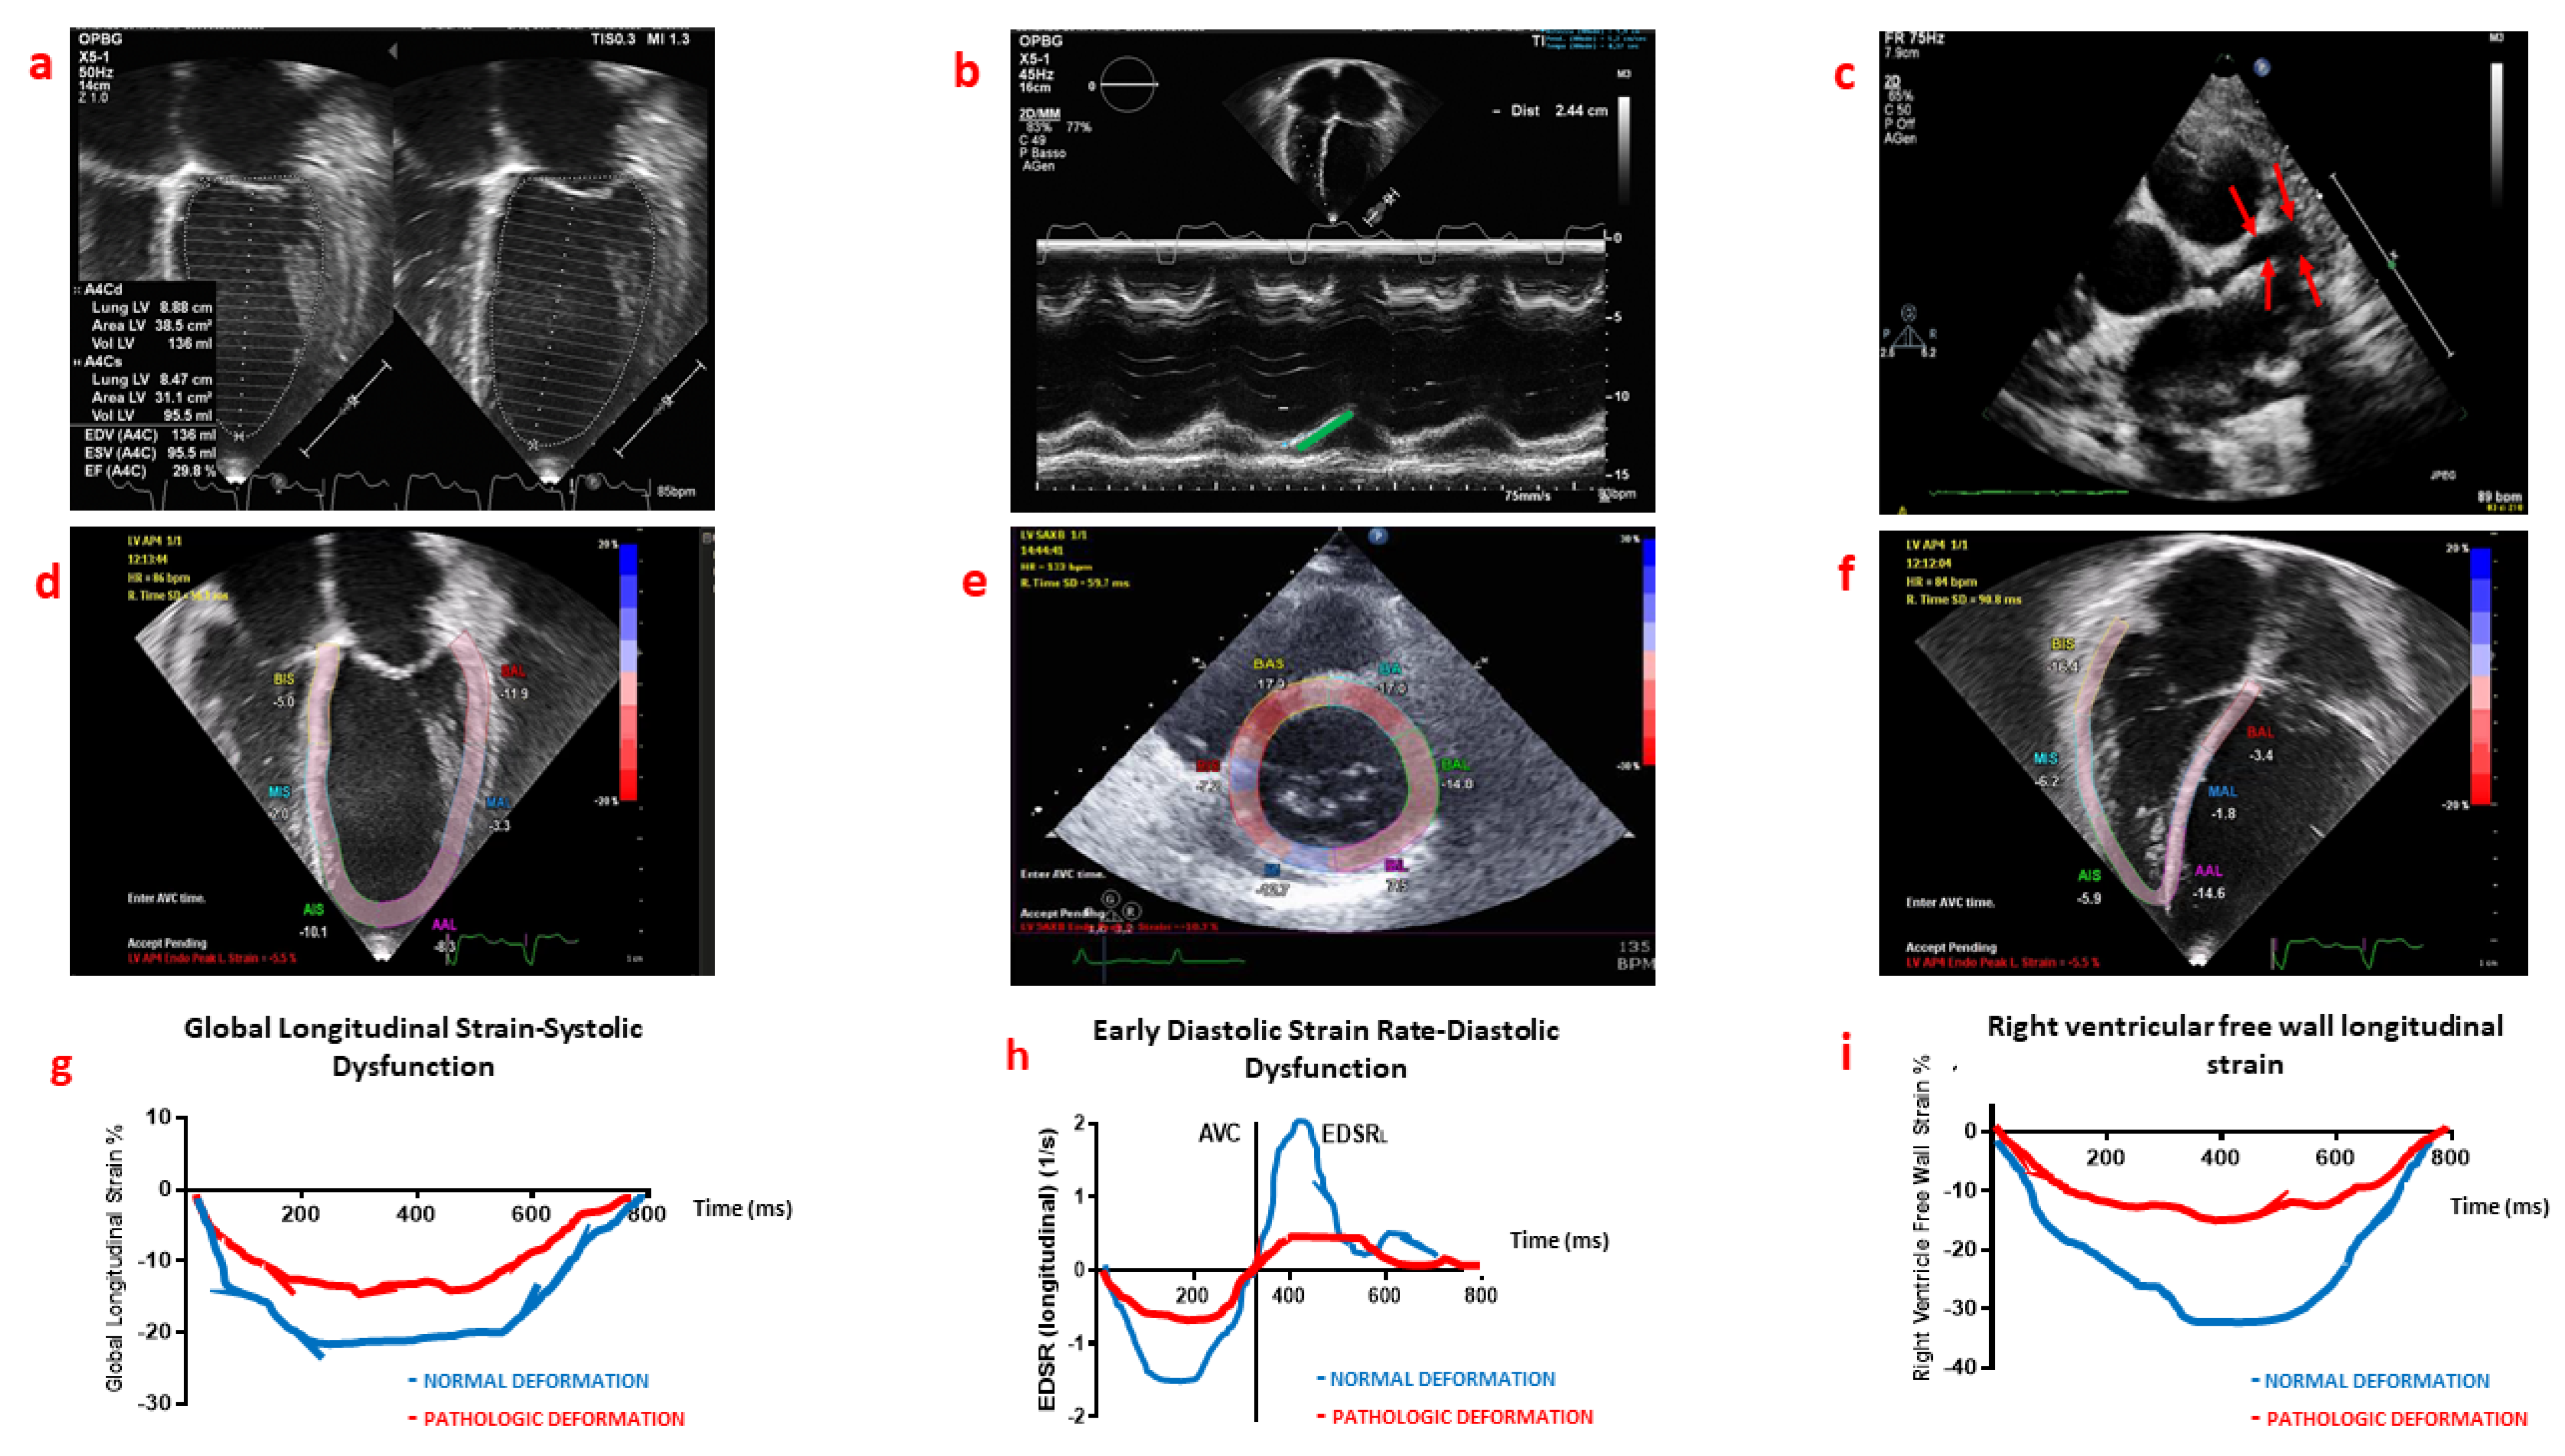

3. Conventional Echocardiography for the Diagnosis, Management and Follow-Up of MIS-C

4. Myocardial Deformation Analysis